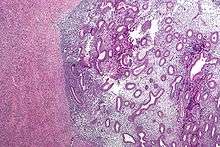

Histopathology

Typical endometriotic lesions show histopathologic features similar to endometrium, namely endometrial stroma, endometrial epithelium, and glands that respond to hormonal stimuli. Older lesions may display no glands but hemosiderin deposits (see photomicrograph on right) as residual.

Immunohistochemistry has been found to be useful in diagnosing endometriosis as stromal cells have a peculiar surface antigen, CD10, thus allowing the pathologist go straight to a staining area and hence confirm the presence of stromal cells and sometimes glandular tissue is thus identified that was missed on routine H&E staining.[57]